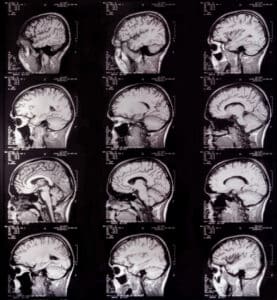

- Prior to a patient’s first session, diagnostic imaging testing is performed to determine the exact location of the tumor